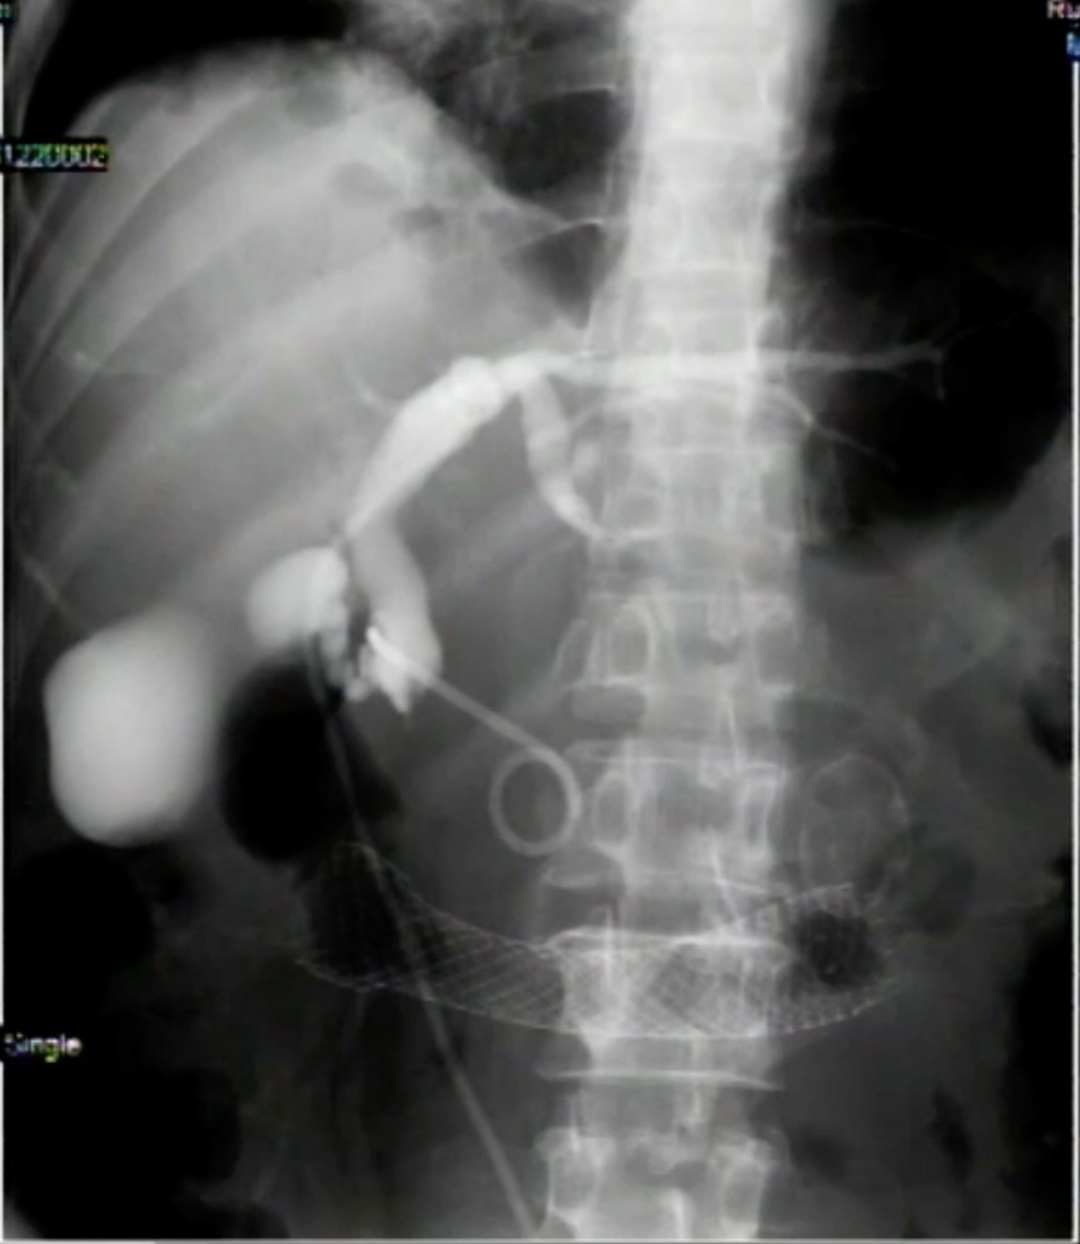

手术当天,随着肠道支架被成功放入,钟先生的消化道按照预估被顺利打通。但是由于肿瘤已经侵犯了胆管开口,常规ERCP下无法放置胆道支架。在内镜超声评估胆道后,张敏敏医生决定改行PLAN B——内镜超声引导下胆道引流,需结合超声、内镜及X线等多种技术,是目前消化内镜最复杂的技术之一。

在祁可技师的精准定位、毕寅莹护师娴熟的配合下,张医生在钟先生的胆管与肠道内放入了一根胆道支架,胆汁迅速从支架内汩汩流入肠腔内,手术成功!

“对下段的胆管梗阻的病人来说,超声内镜引导下胆道引流术是一种新的选择。”消化内科主任邹多武表示,传统的引流方式会造成胆汁的丢失、脂溶性维生素的缺乏,而且管子容易堵、脱落、造成感染,胆汁还容易渗漏,病人生活质量很低。现在通过超声穿刺,胆汁引流到胃肠内,走的是和原来生理状态下的类似的路,可以有效避免炎症的发生,提高病人生活质量。